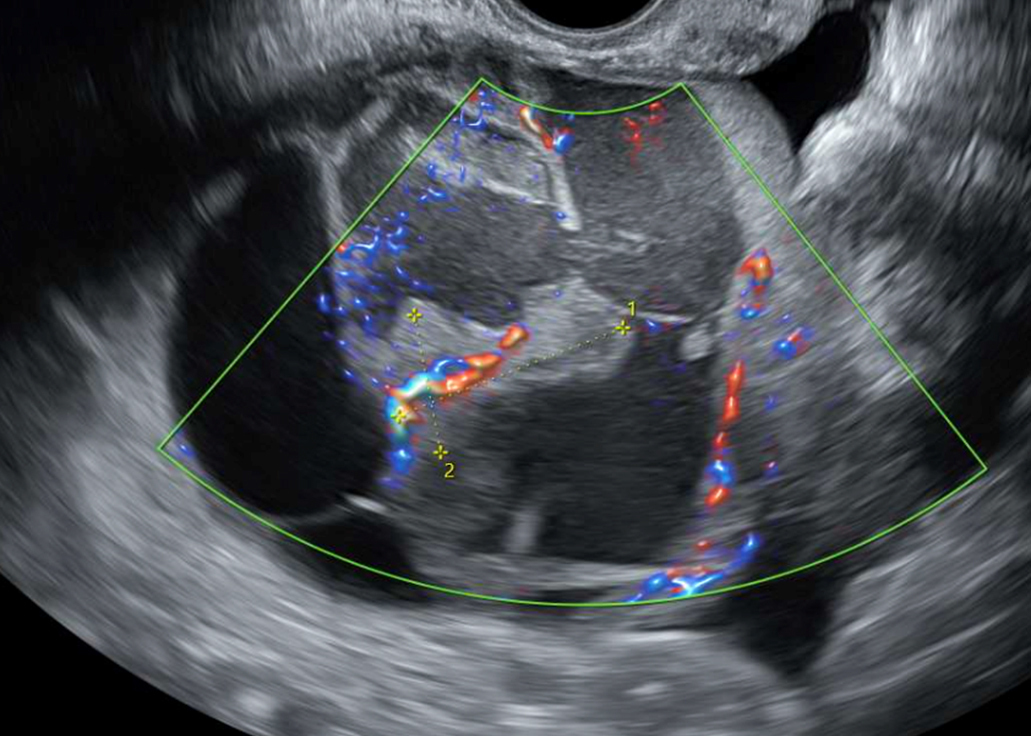

Un flux Doppler normal n’exclut pas la torsion ; il peut persister un flux artériel ou veineux résiduel, il s’agit d’un mauvais signe échographique pour le diagnostic.

La triade douleur pelvienne aiguë brutale, nausées, vomissements est évocatrice de torsion d’annexe chez la femme en âge de procréer. La figure 2 illustre les différents critères échographiques d’une torsion annexielle (ovaire augmenté de volume [> 4 cm], souvent porteur d’un ou plusieurs kystes, hyperéchogène compte tenu de l’œdème, avec parfois l’absence de vascularisation au Doppler, et un ovaire controlatéral habituellement d’aspect normal).

Figure 2 (Rodolphe Matias de Sousa, La Revue du Praticien)